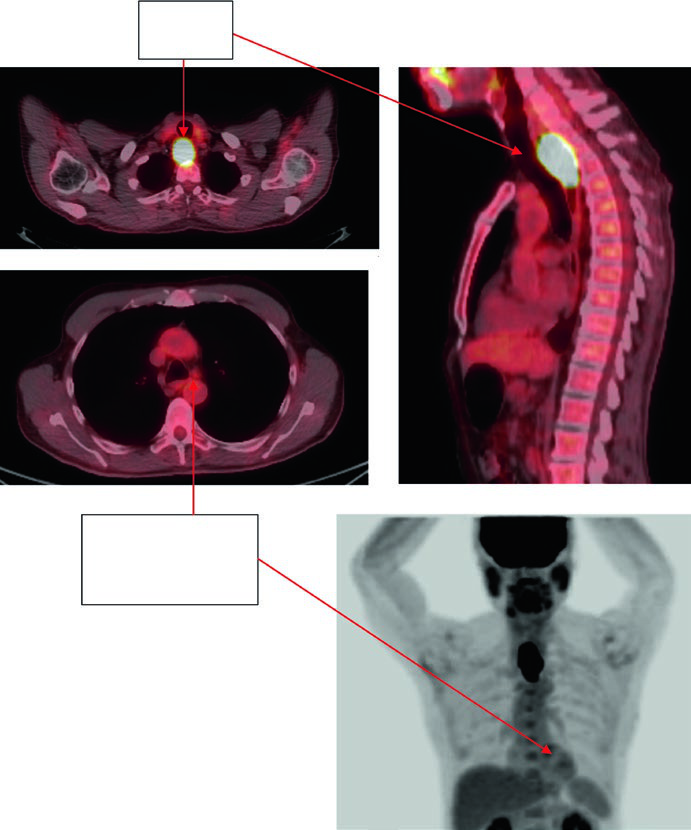

Caso 4: Adenocarcinoma de JGE — 59 anos, uT3N2

Paciente de 59 anos com adenocarcinoma de JGE uT3N2. O PET demonstrou linfonodos paraesofágicos captantes e tumor primário localizado entre 36 e 40 cm dos incisivos. O corte sagital da TC de planejamento mostra o ITV refletindo o movimento do GTV, com CTV cobrindo 3–4 cm acima do ITV. Volumes: estômago/duodeno (verde escuro), GTV nodal (verde claro), GTV esofágico (vermelho), ITV (rosa), CTV (laranja), PTV 50,4 Gy (ciano). Os linfonodos paraesofágicos foram incluídos no campo de tratamento.